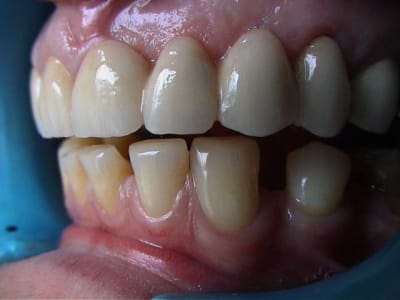

allez Hop 1 cas dont je suis un peu content

fait en Mars 2001

cette pauvre accidentée en 95 avait un bridge ( refait par le même praticien sur ordre de la MGEN ) qu'elle tenait avec la langue ( si si ! )

definitif 03/2001